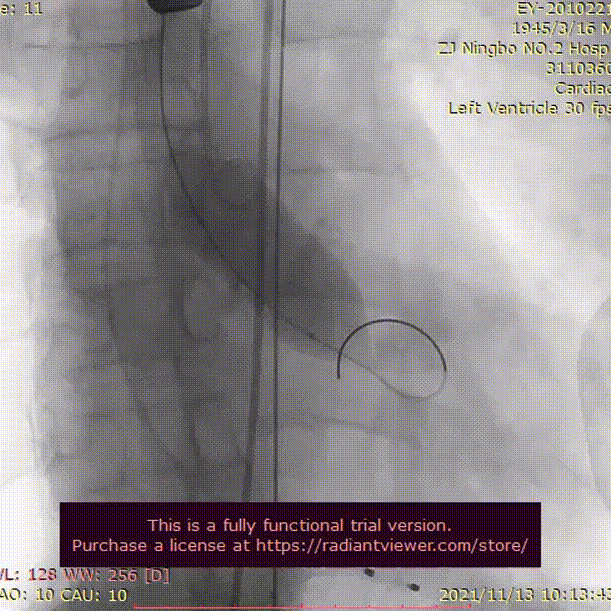

主动脉根部造影评估

20 mm球囊预扩

瓣膜成功植入后,造影提示瓣膜未能完全伸展。术者团队依照既定策略予以20 mm球囊后扩再行主动脉根部造影,提示治疗效果得到改善。

瓣膜完整形态